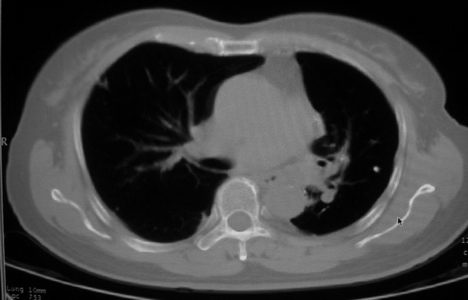

以下是引用李衡钧在2008-7-24 14:24:00的发言:[br]左侧胸廓变小,左肺上叶见大面积致密阴影,其内有空洞及不规则钙化。上纵隔略向左移位,上肺胸膜增厚。左肺门及纵隔淋巴结增大。右肺见散在的致密结节影。[br]印象:继发性肺结核。